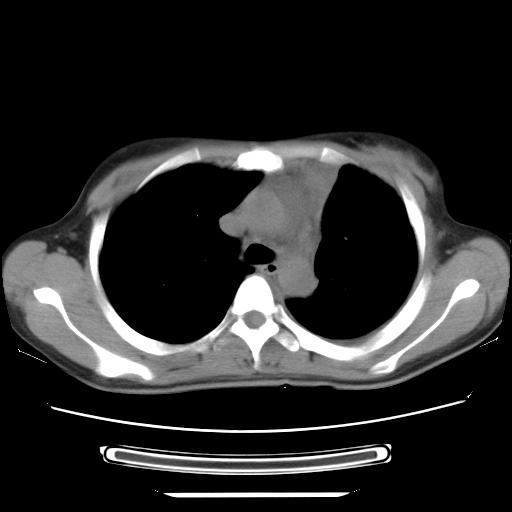

女,29岁,胸部不适,在外院胸片提示胸腔积液,到我院ct检查。

纵膈窗

1、左侧包裹性积液伴叶间积液 2、右肺多发结节考虑增殖结节

左侧纵隔胸膜包裹性积液、左侧胸腔积液、胸膜肥厚粘莲,考虑结核性胸膜炎

左肺上叶不张,左侧胸水,叶间裂积液,纵隔淋巴结,脾脏钙化,考虑左肺上叶支气管内膜结核,结核性胸膜炎,脾结核

考虑:1.两肺tb;2.左侧胸膜炎、胸腔积液。

考虑两肺结核,左侧包裹性积液,叶间积液。

支持两肺继发性肺结核,左侧胸膜腔包裹性积液、胸膜肥厚,脾内多发钙化(结核钙化)。

右肺多发结节。左胸腔多发包裹性积液。